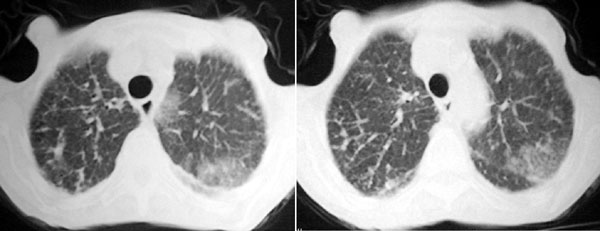

f 76 间断咳嗽 咳痰1年余 发热不明显 身体削瘦

征象:

1、右肺中叶近肺门区可见一空洞样病灶,内壁不规则,有与邻近支气管相通的征象,其外侧大片肺组织软组织状实变,余肺可见散在点、片絮状密度增高影,肺纹理可见明显增粗及串珠样改变;

2、纵隔气管前、隆突下、内乳组、心右前间隙以及右侧腋窝内均可见肿大的淋巴结节;

3、右侧胸膜增厚粘连,胸腔少量积液征像;

4、其它征像略。

诊断意见:

1、右侧中央型(空洞性)肺癌并双肺受累(包括转移、阻塞性炎症、癌性淋巴管炎);纵隔、右侧腋窝内淋巴结肿大、转移;右侧胸膜增厚粘连,胸腔少量积液;

2、双上肺陈旧性结核。

3、慢性支气管炎、肺气肿。